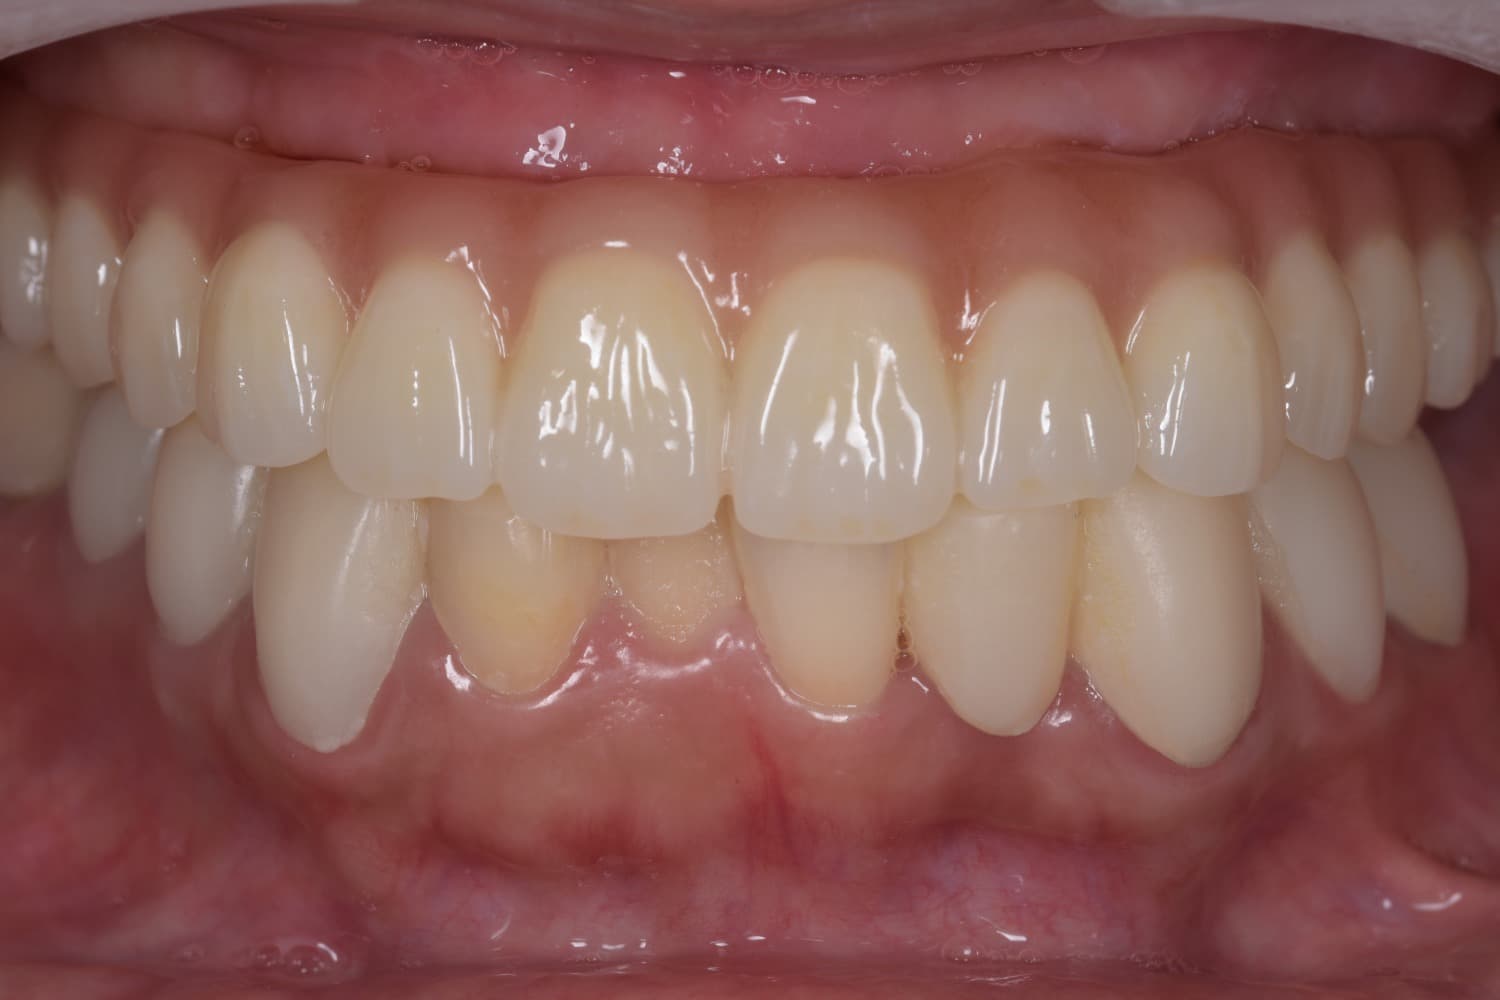

上顎の全顎の即時インプラント(40代女性)

After

上顎の全顎の即時インプラント(1Dayトリートメント) 仮歯まで1日で入ります。 ※治療後も定期的なメンテナンスは必要

年齢

40代

性別

女性

主訴

歯が欲しい、インプラントを入れたい

治療期間

3ヵ月

治療回数

5回

費用

300万円

副作用・リスク

顔面の腫れ